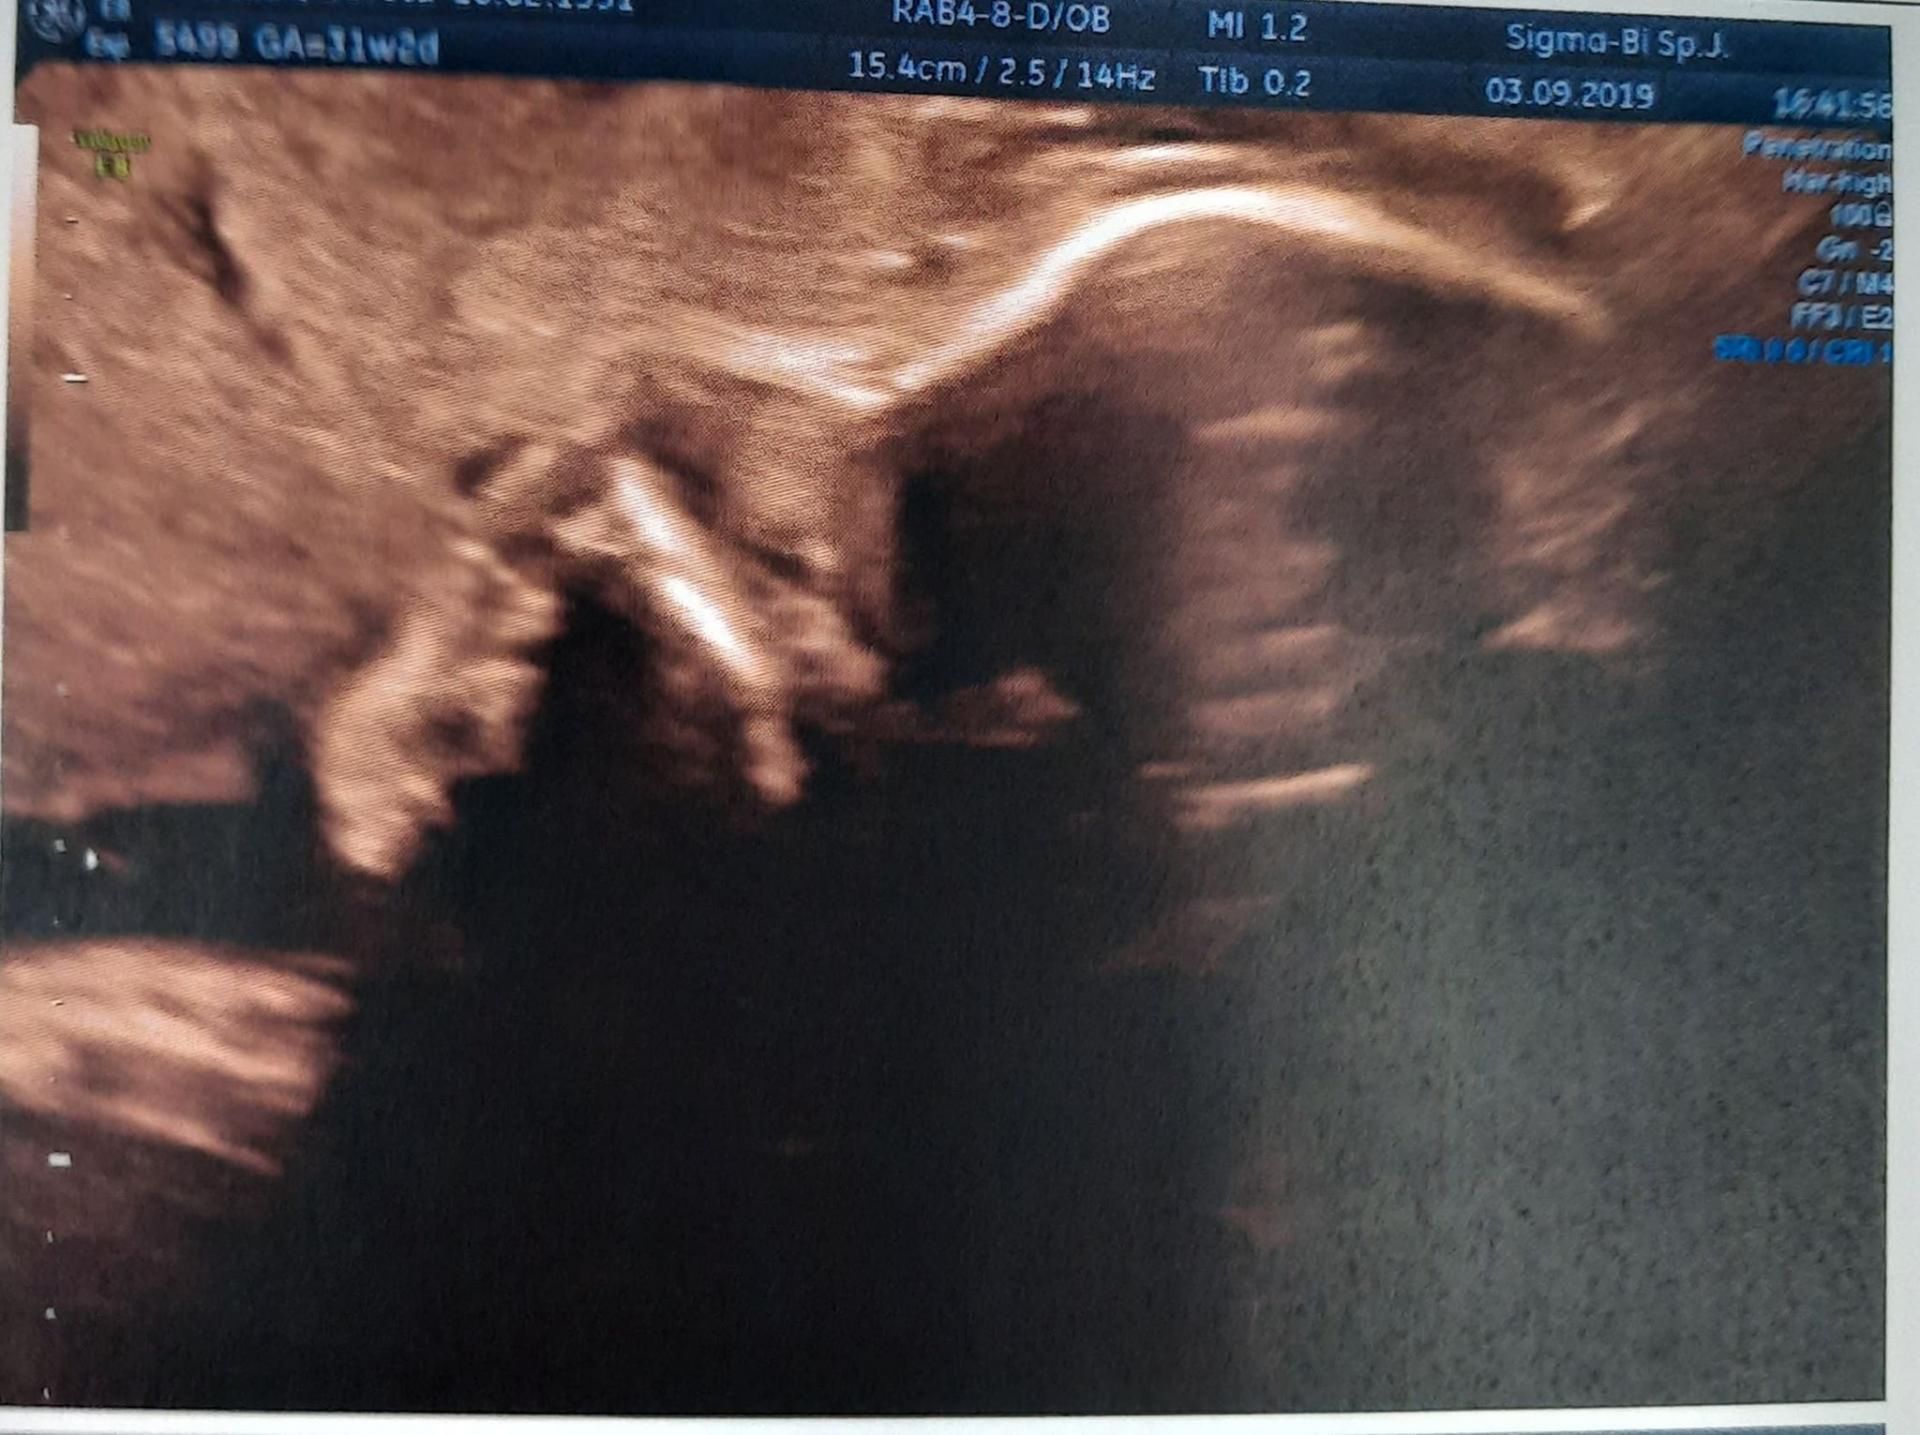

W trakcie kolejnego badania USG, w III trymestrze ciąży, lekarz ponownie stwierdził hipoplastyczną kość nosową.

Szanse na urodzenie zdrowego dziecka wynosiły 1 proc.

Szanse na urodzenie zdrowego dziecka wynosiły 1 proc. © Materiały własne

- Wtedy było mi już wszystko jedno. Nawet zaczęłam żartować. Powiedziałam dla rozluźnienia: “będzie miała mały i zgrabny nosek”. Potem po prostu czekałam do rozwiązania - przyznaje kobieta.